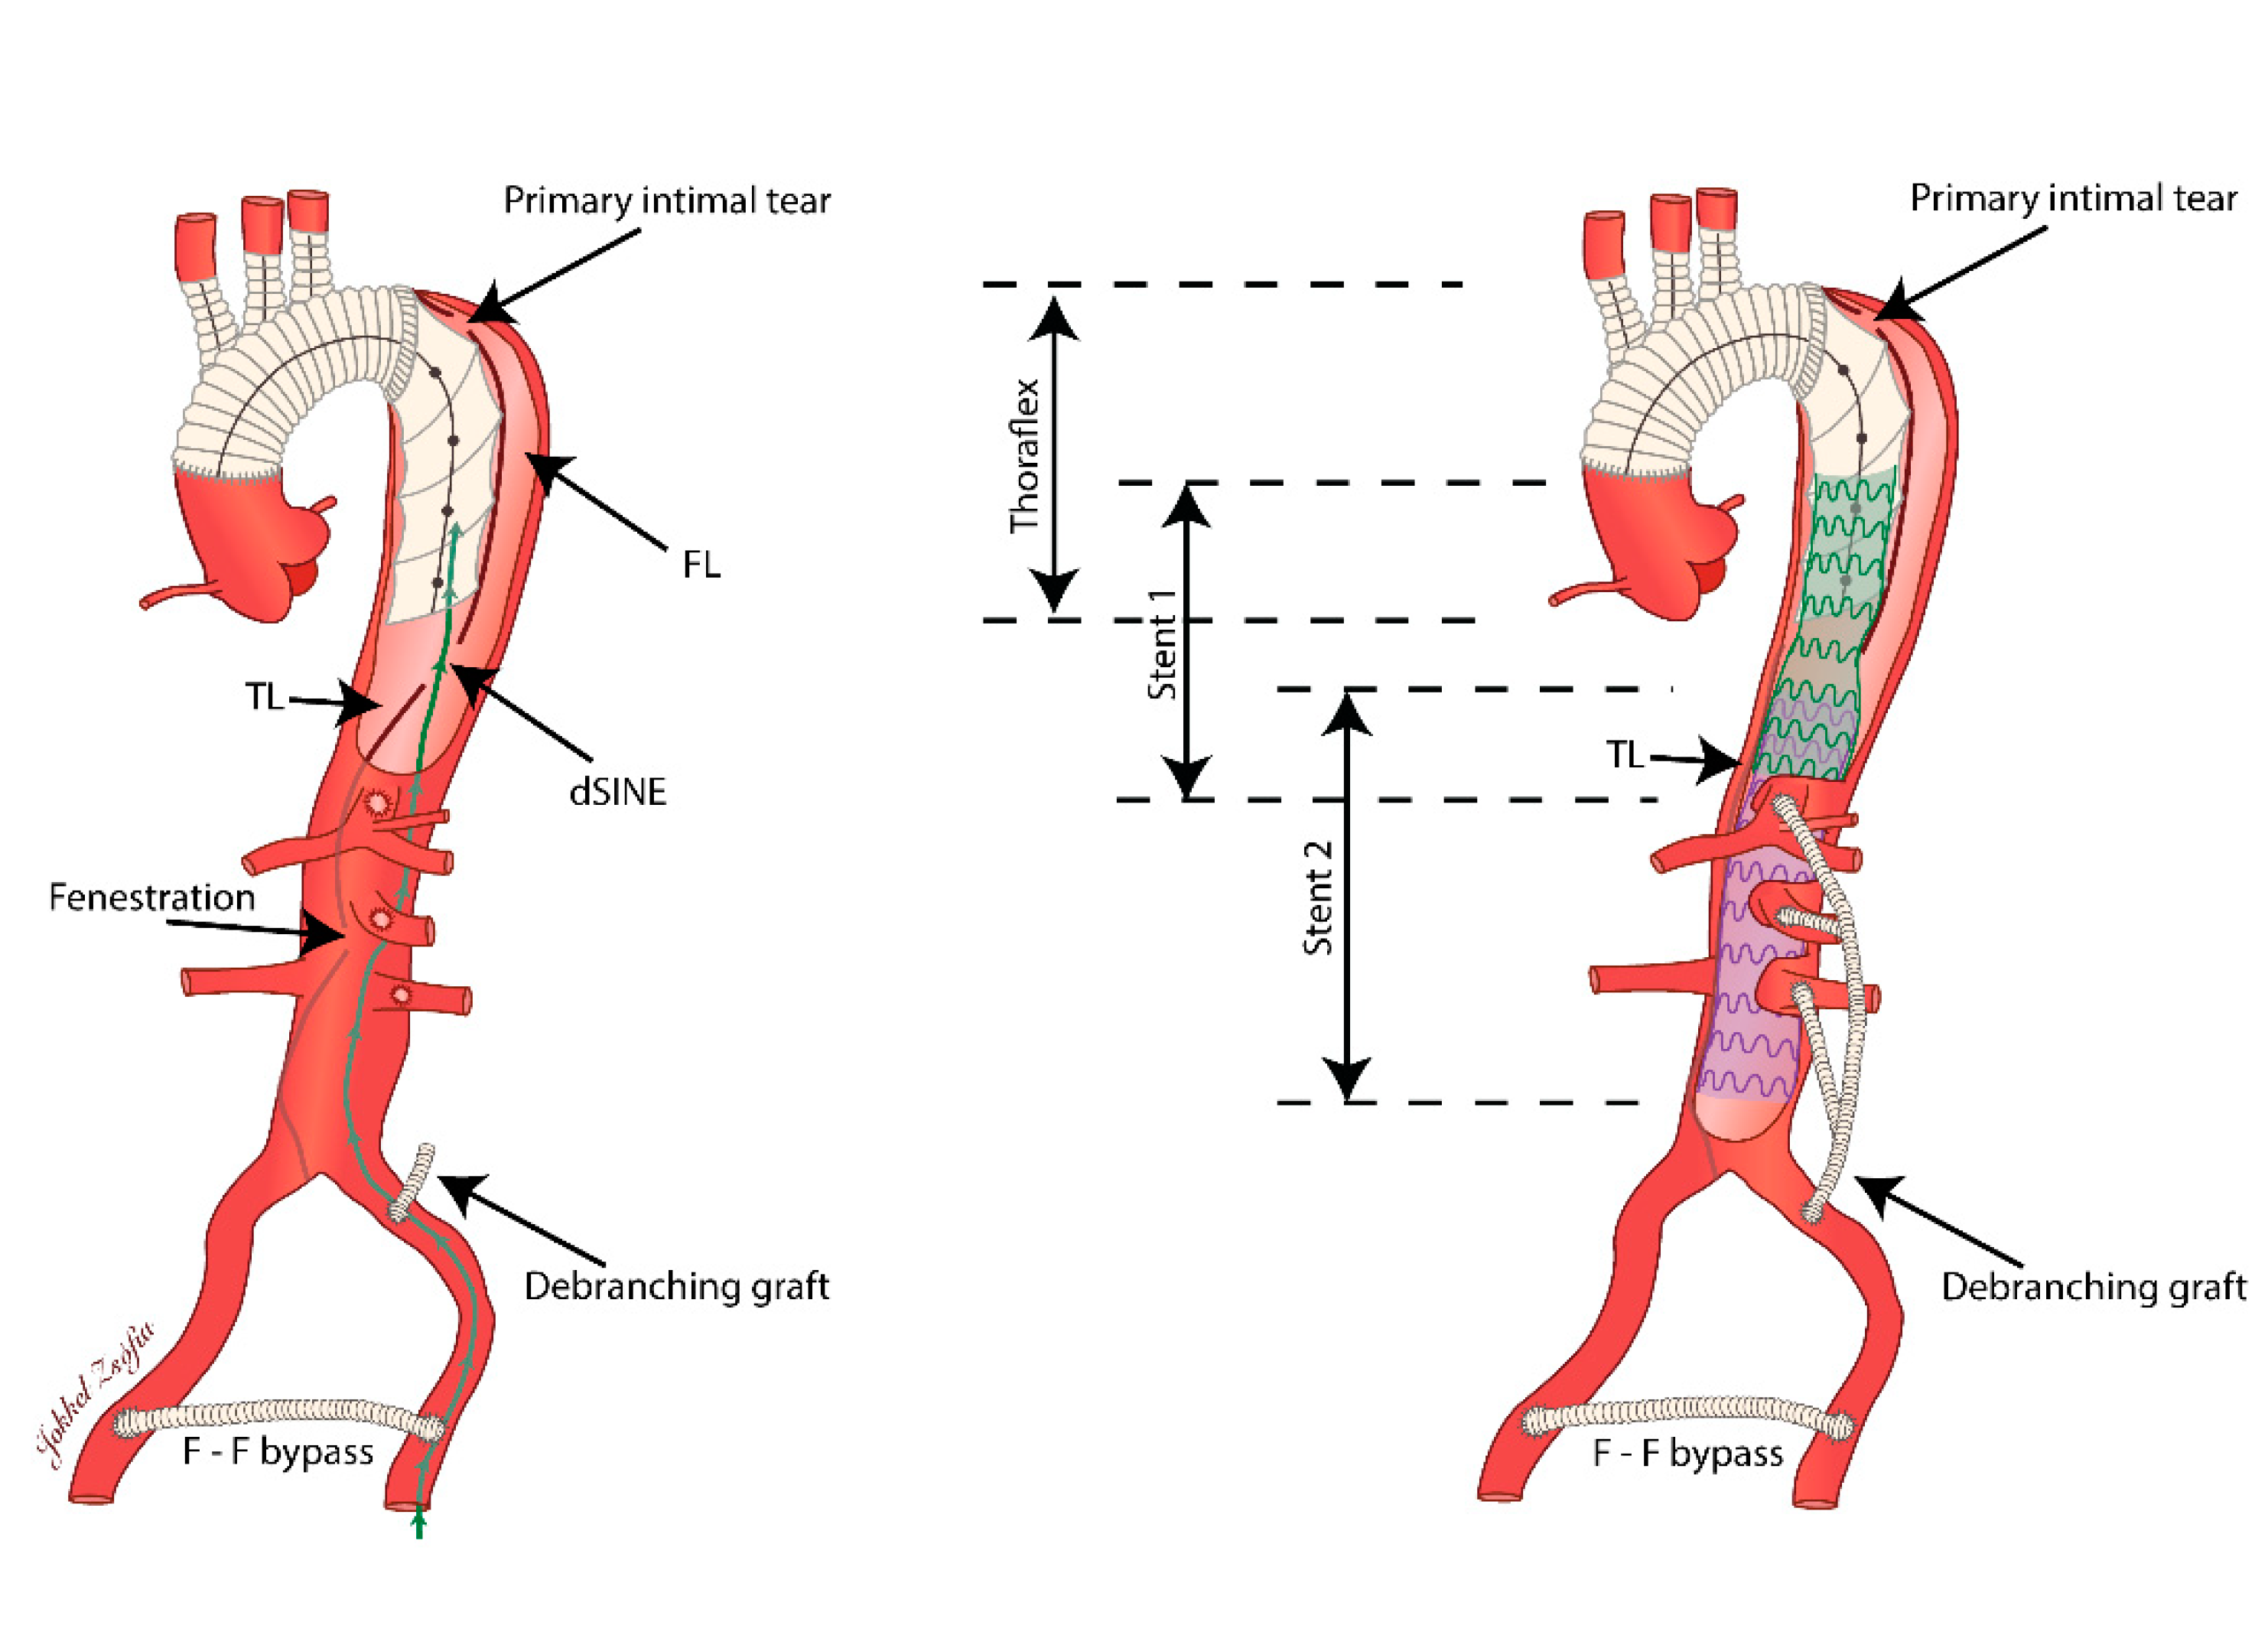

Staged Hybrid Repair of a Complex Type B Aortic Dissection

2. Case Presentation

3. Discussion

4. Conclusions